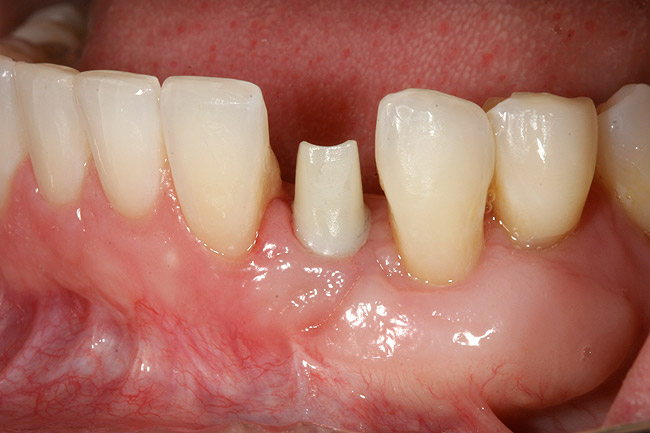

Figure 4  Vertical ridge defect in site No. 22.

Figure 4

Figure 5  Horizontal ridge defect in site No. 22.

Figure 5

Figure 6  Mucogingival and residual defect after removal of implant in site No. 22.

Figure 6

The patient had no medical concerns and had a history of an implant placement in December 2002 when she was 25 years old. In February 2005, she presented with a mobile implant and an associated advanced peri-implantitis. Radiographic review at the initial examination demonstrated significant destruction of the dentoalveolar ridge around the implant as well as around the adjacent natural dentition. Emergency-based treatment involved surgical implant removal only and debridement of the infection (Figure 4 and Figure 5). Following uneventful healing, an advanced ridge defect was apparent at the edentulous site and moderate and advanced attachment loss noted at No. 22D and No. 21M, respectively (Figure 6 and Figure 7). This case demonstrates bone loss of two separate origins: lack of bone because of tooth agenesis and destruction of bone from inflammatory peri-implantitis.